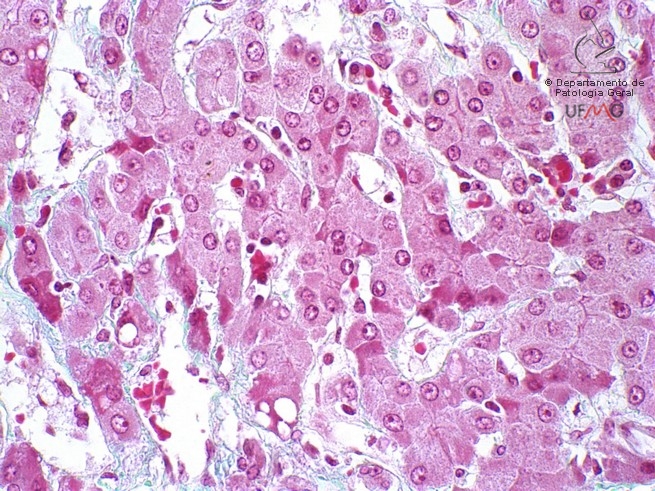

Reparo 60x

Fígado

Coloração: Tricrômico de Gomori

Cirrose hepática